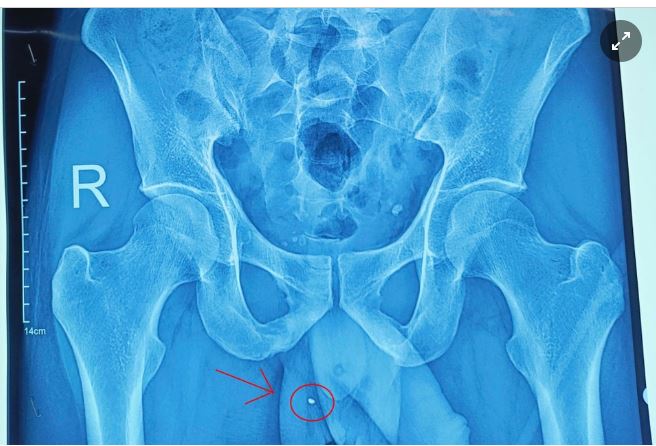

Đang sử dụng súng bắn đinh hạt nổ để làm việc, người đàn ông bất ngờ bị mảnh kim loại văng ra từ súng đâm xuyên vào dương vật.

Ảnh chụp mảnh kim loại nằm trong vùng bìu người bệnh. Ảnh: BVCC.

Người đàn ông 33 tuổi, ở huyện Chiêm Hoá, tỉnh Tuyên Quang, đến khám tại Bệnh viện Đa khoa tỉnh Tuyên Quang trong tình trạng sưng nề, chảy máu vùng dương vật và bìu bên phải.

Bệnh nhân kể lại trong quá trình làm việc, anh sử dụng súng bắn đinh. Bất ngờ, mảnh kim loại từ súng văng ra và đâm xuyên vào cơ quan sinh dục.

Ngay khi nhập viện, người bệnh được làm các xét nghiệm và lập tức chuyển lên phòng mổ cấp cứu. Trong quá trình phẫu thuật, ê-kíp phát hiện bệnh nhân có vết thương "xuyên táo" tinh hoàn phải (từ đuôi mào tinh hoàn đến đầu mào tinh hoàn), đang rỉ máu.

Các bác sĩ đã phẫu thuật lấy ra dị vật kim khí (kích thước khoảng 4 mm), sau đó cầm máu kỹ, bảo tồn tinh hoàn và đặt 1 dẫn lưu cho bệnh nhân.